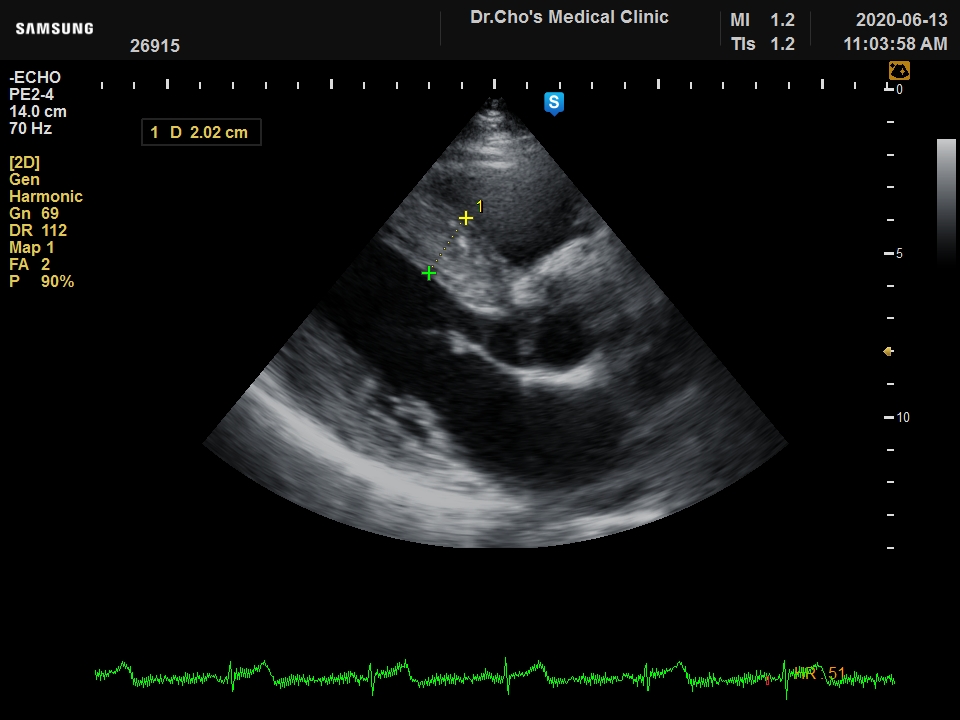

ÃÊÀ½ÆÄ°¶·¯¸®

¿ì½É½Ç °æ...

ºñÈļº ½É...